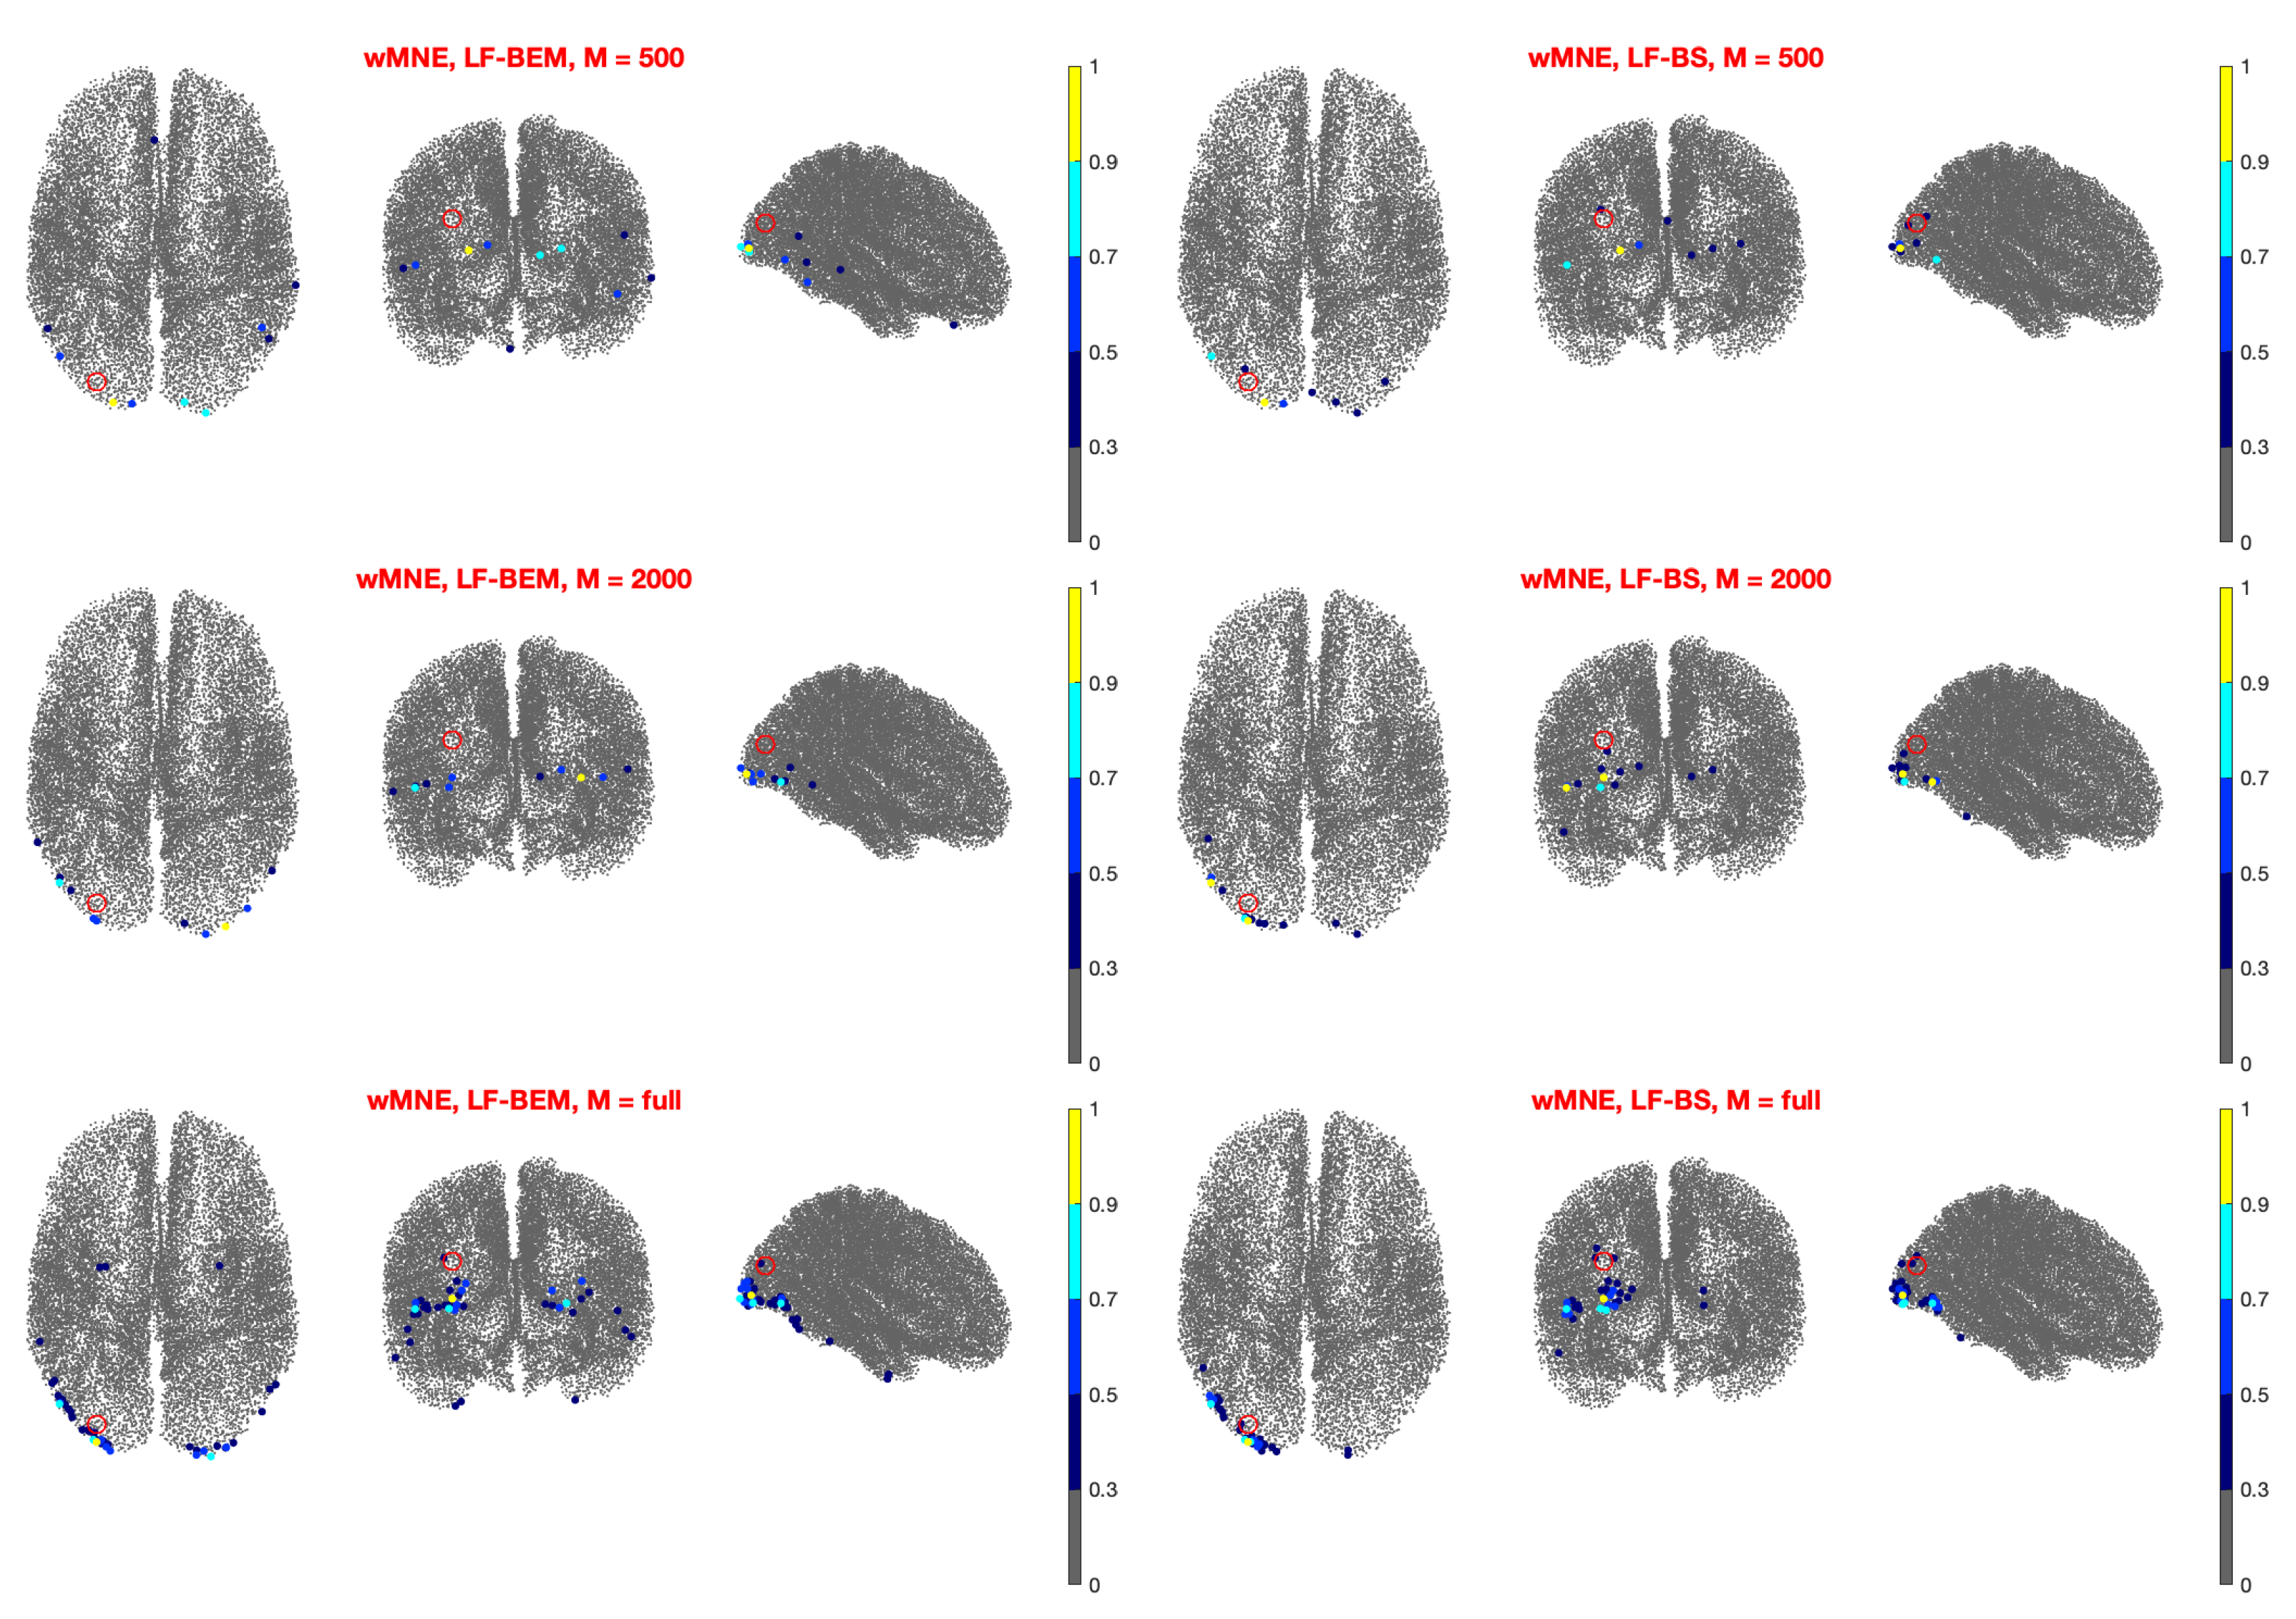

- Left Visual Case (Figure 4): Also in this case the results depend slightly on M. For and the DLE is about 1 cm or less for all the methods except dSPM coupled with LF-SP.

3.2. Real Data Analysis